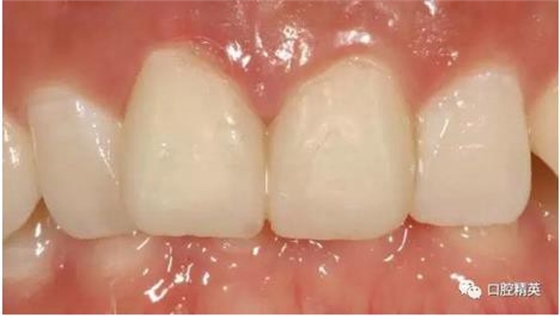

修復(fù)體戴入

口內(nèi)正側(cè)位及切端特寫(xiě)

從側(cè)位照可看出遠(yuǎn)中切角略有回收

對(duì)比來(lái)看基本達(dá)到患者預(yù)期

有一點(diǎn)不足之處在于齦緣的高低不完全一致,補(bǔ)救辦法同上——激光輕掃